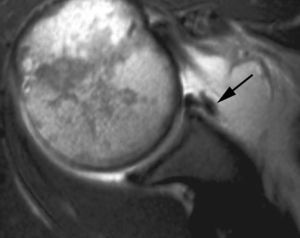

Rotura simple del labio glenoideo posterior

Esta lesión se produce a consecuencia de una dislocación posterior y puede acompañarse de una fractura por impactación de la parte anterior de la cabeza humeral (Hill Sachs invertido) (fig. 13).

Fig. 13.--Rotura del labio glenoideo posterior. Artrorresonancia axial T1 con supresión grasa que revela una rotura del labio glenoideo posterior (flecha).